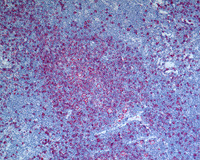

Figure 1: H&E images

HE images showing nodular architecture in many areas. Note the tumor-cell rich area in the image on the top right within the nodules.